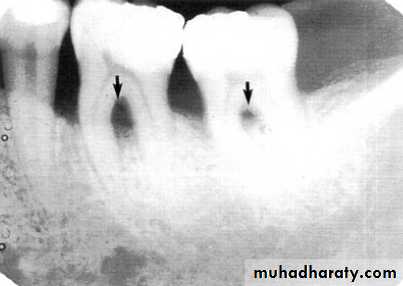

Direction :

Intercrestal bone should be parallel with line dawn from the CEJ of one tooth to that of the contacting tooth.

1. Horizontal bone loss:- When loss occurs on a plane that is parallel with a line drown.

2.Vertical bone loss:- when there is greater bone loss in one tooth than on the adjacent tooth, so the bone level is not parallel with a line joining the CEJ.